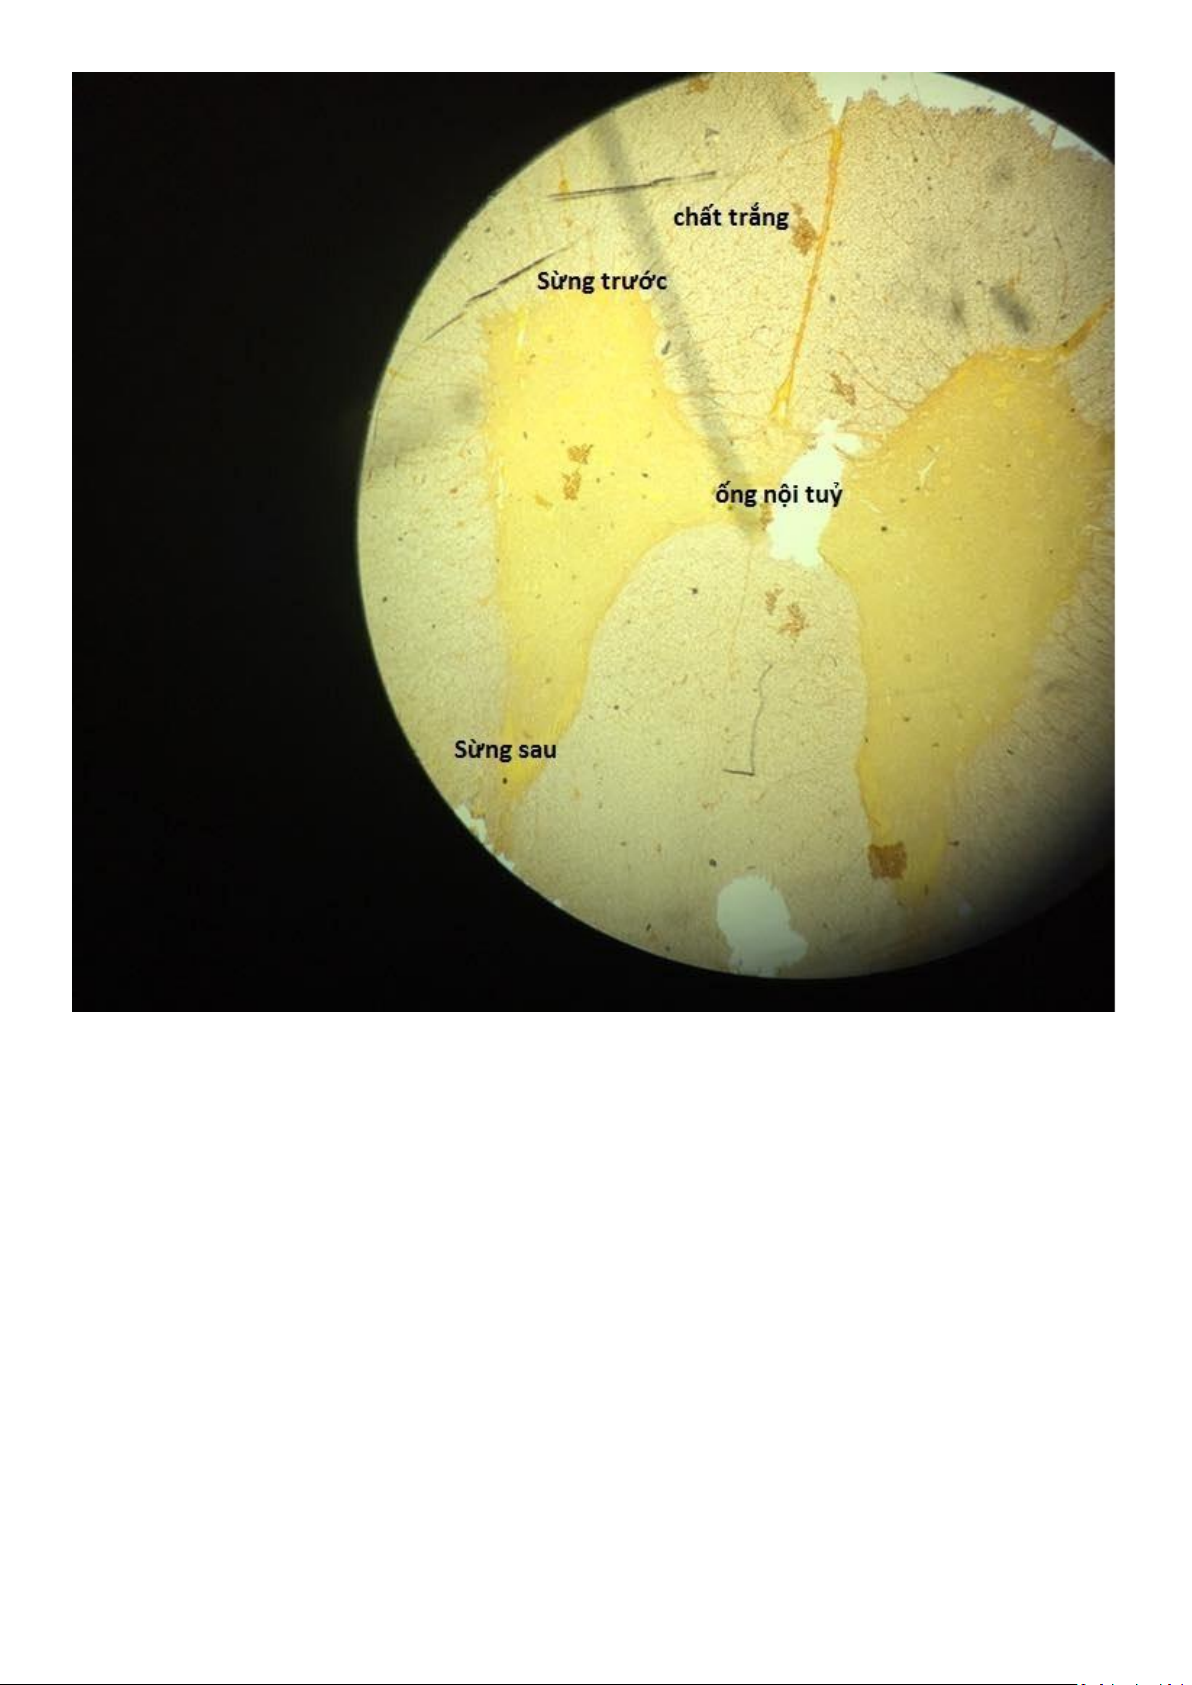

i ể u m ô t r ụ g i ả t ầ n g – T h à n h t h ự c q u ả n lOMoAR cPSD| 59691467 lOMoAR cPSD| 59691467 Tuỷ gai x10 lOMoAR cPSD| 59691467 Tuỷ gai x40 lOMoAR cPSD| 59691467 lOMoAR cPSD| 59691467 T